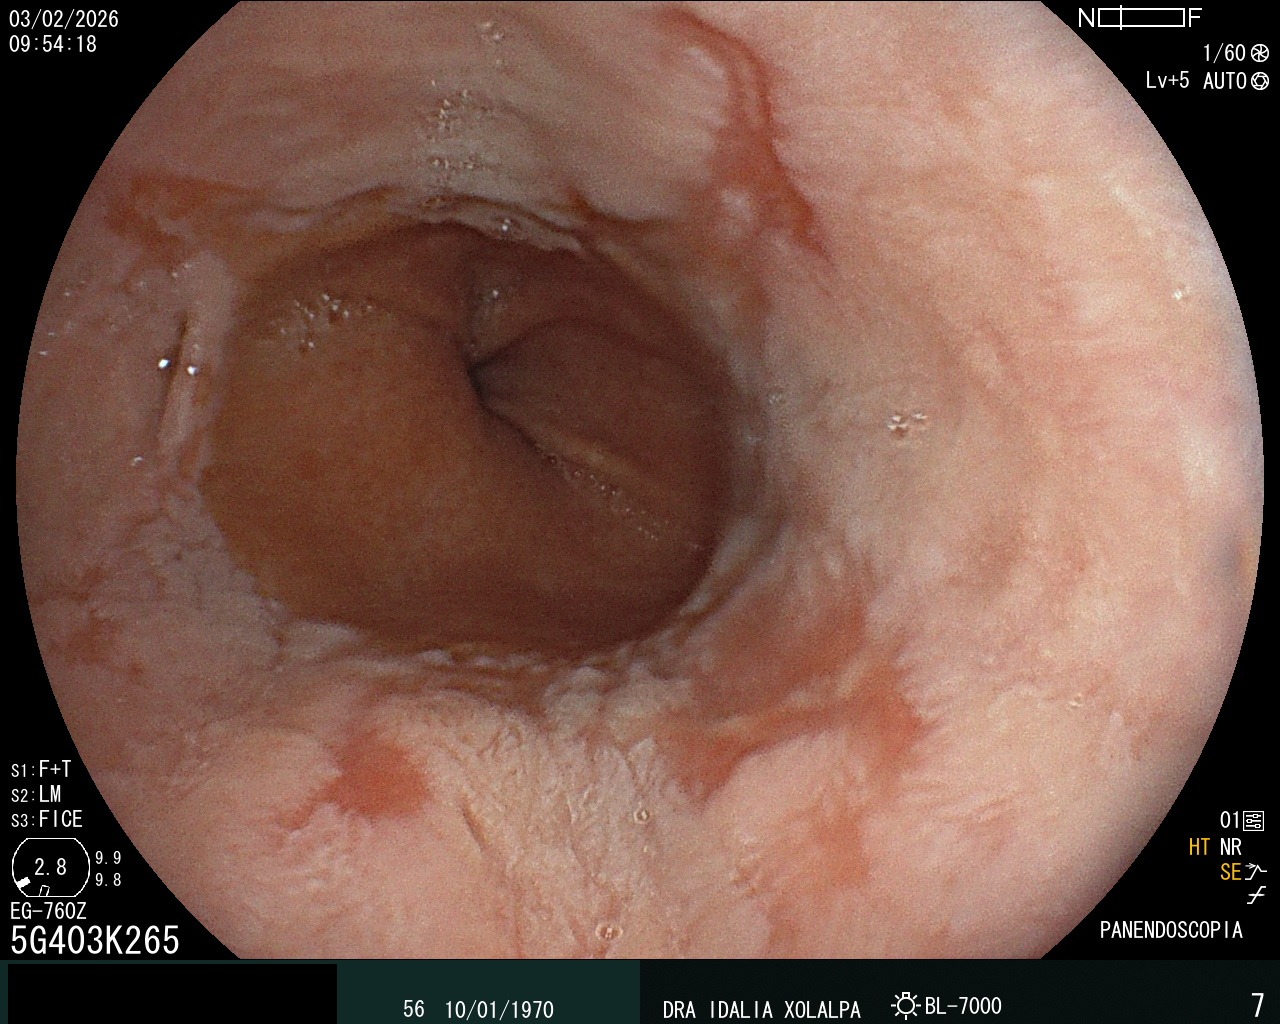

Colon Normal

Vista de un colon sano durante colonoscopia

Hernia Hiatal

Identificación de hernia hiatal por endoscopia